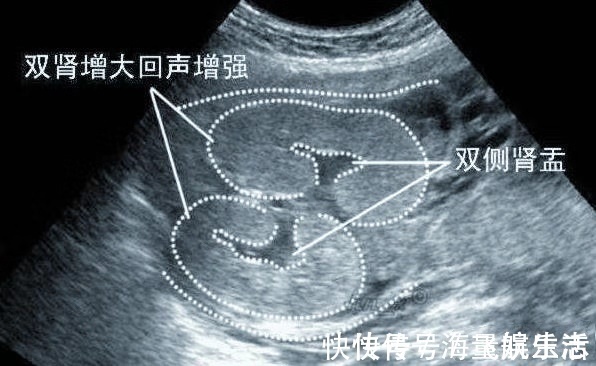

所谓的肾盂,是指肾与输尿管的连接处;而肾盂分离,就是肾脏的尿液无法正常地流入膀胱。当尿液积存到一定的时候,就会出现肾盂分离。胎儿肾盂分离的原因有两个,一个是由于输尿管的一部分狭窄而导致尿液流动停滞,另一个是积存在膀胱中的尿液朝肾脏逆流而造成。

胎儿双肾盂分离多半发在孕中期与孕晚期。孕妈听到胎宝宝肾盂分离或许有会很焦虑,其实不必过于担心。胎儿肾脏轻度分离是很常见的,据统计显示,100个胎儿之中就有一个胎儿会出现肾盂轻度分离的情况,而且大部分会随着孕周增长而逐渐消失。

正常来说,肾盂分离<10mm,为生理性,不必特别处理,孕妈定期检查就好。但是怀孕30周后,肾盂分离≥10mm,则可能要考虑肾积水了,一个小时后需要再进一步确认,检查结果还是一样的话,那医生就要给胎儿做相关的检查,必要时进行治疗,据说这种情况600-800个胎儿之中有1个,而且有99?小宝宝在出生后可治好。像题主这样,孕早期就有,孕晚期还没消失而且肾盂分离≥10mm,则要跟医生沟通一下了。